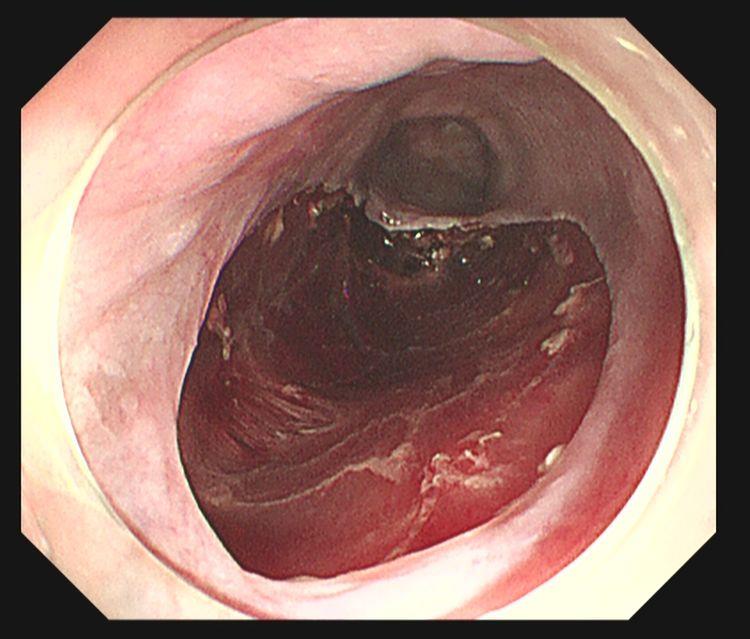

术前内镜下白光示:不规则片状黏膜略粗糙,表面发红

内镜NBI示:病变黏膜呈茶褐色改变

卢戈碘染示:病变区域呈不染区,粉红征阳性